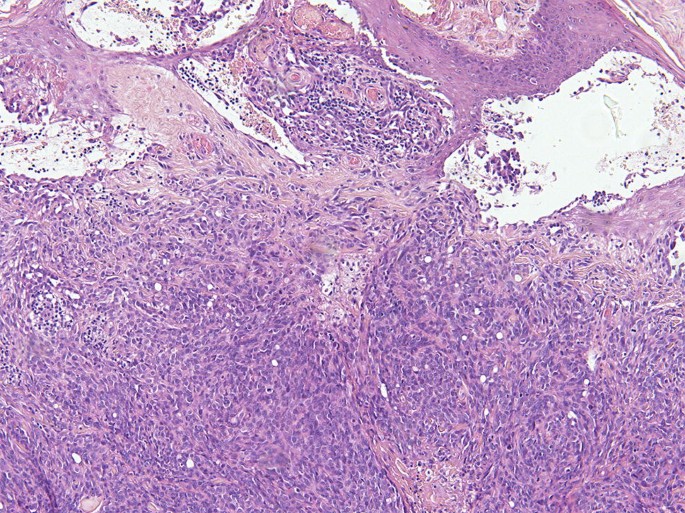

Vascular tissue neoplasm refers to a tumor that originates from the body's vascular system, which includes the blood vessels (arteries, veins, and capillaries) and the lymphatic system. The vascular tissue neoplasm market is experiencing significant growth due to several key market drivers. Firstly, advancements in medical research and diagnostic technologies have played an important role in the expansion of this market. With improved tools for early detection and accurate diagnosis of vascular tissue neoplasms, healthcare professionals can provide more effective treatment options to patients. Additionally, an aging population is contributing to the increasing prevalence of vascular tissue neoplasms. This demographic shift has raised demand for treatments and therapies, thereby boosting the growth of the vascular tissue neoplasm market.